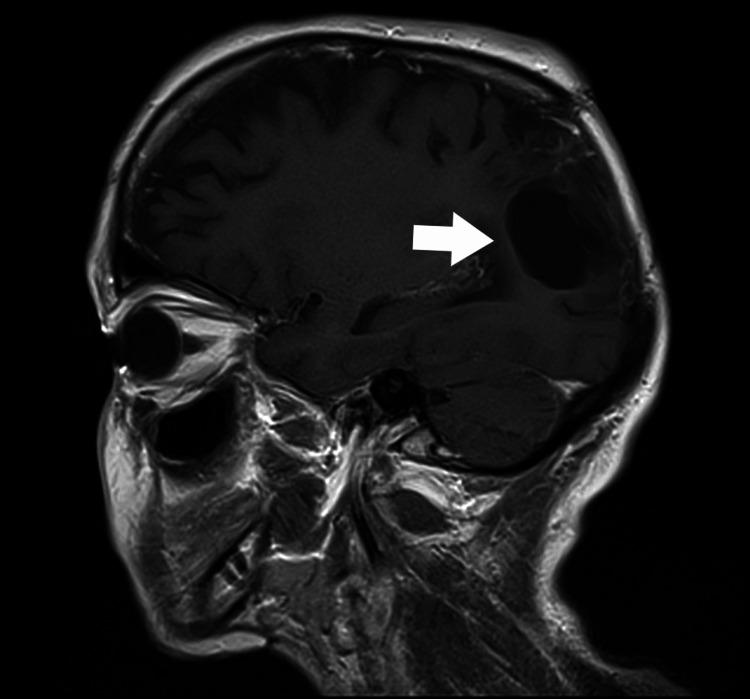

A brain abscess (BA) is a purulent infection of the central nervous system and can be associated with dental procedures. The paper presents a case of a patient diagnosed with an odontogenic BA. On admission, the patient was awake, alert, and oriented (Glasgow Coma Scale 15). The patient reported undergoing excision and drainage of an abscess in the submandibular area three years earlier. An MRI of the head showed a mass lesion (34x19x25 mm) located in the right parieto-occipital region, and an abscess was suspected. During the procedure, puncture and evacuation of the contents of the abscess in the right parieto-occipital area were performed. Oral microorganisms, including and , were isolated from the brain pus. A thorough radiographic and dental examination should be conducted during hospitalization in these patients. Always evaluate for periapical pathology in unexplained BAs, even in the absence of oral symptoms.

脑脓肿(BA)是中枢神经系统的化脓性感染,可能与牙科手术有关。本文介绍了一例被诊断为牙源性脑脓肿的患者。入院时,患者清醒、警觉且定向力正常(格拉斯哥昏迷量表评分为15分)。患者报告三年前曾接受下颌下区脓肿的切除和引流手术。头部MRI显示右顶枕区有一个肿块病变(34×19×25mm),怀疑为脓肿。手术过程中,对右顶枕区脓肿内容物进行了穿刺和引流。从脑脓液中分离出包括[具体微生物名称1]和[具体微生物名称2]在内的口腔微生物。对这些患者住院期间应进行全面的影像学和牙科检查。即使没有口腔症状,对于不明原因的脑脓肿也应始终评估根尖周病变情况。